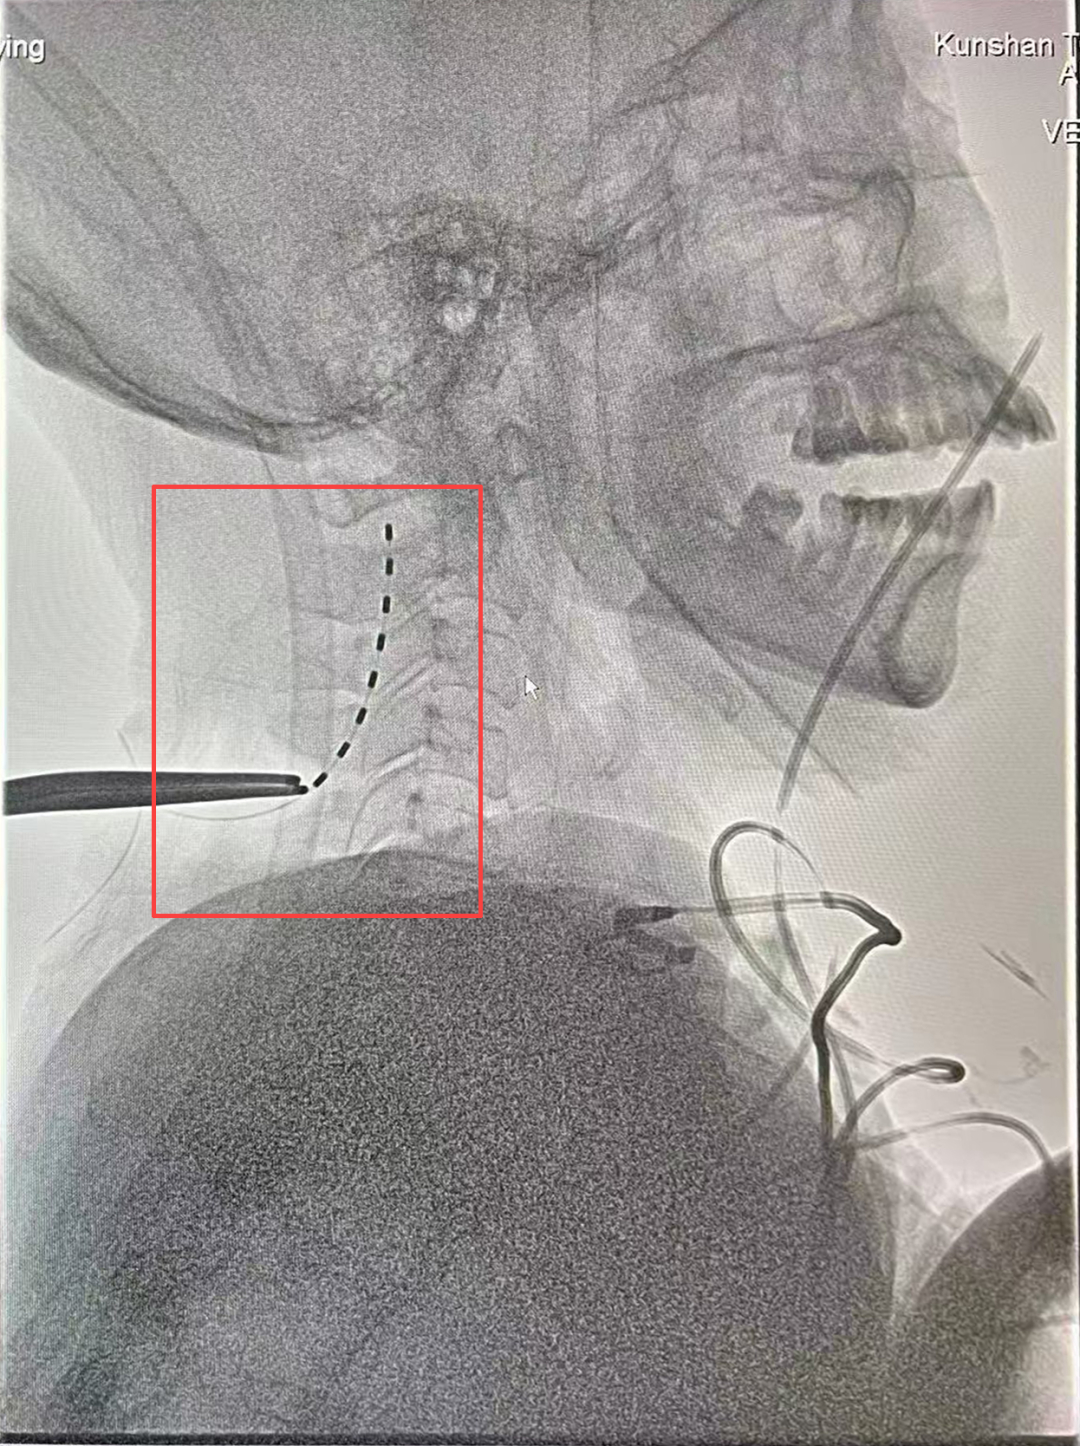

几周后,神经外科陈龙主任医师与陆维主治医师在王文华主任的指导下,为张女士实施临时脊髓电刺激术(ST-SCS)。

术中,电极被精准植入颈髓C2-C4水平硬膜外,通过脉冲刺激激活上行网状系统,促进脑皮层代谢与电活动。

▲神经外科团队为张女士行临时脊髓电刺激术(ST-SCS)

一个月后,在王文华主任的指导下陈龙主任医师与陆维主治医师为张女士在全麻下行SCS永久植入术

▲术后CT:电极植入位置精准